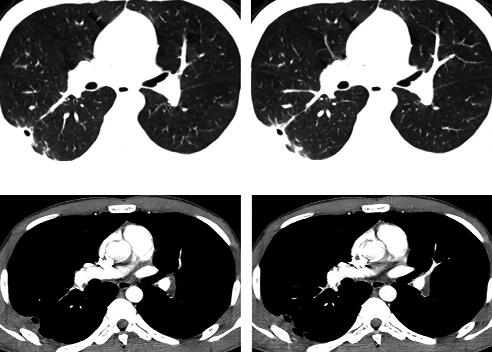

3.胸部CT:

右肺下叶外后基底段散在斑片及片状渗出影,部分病灶呈楔形,尖端指向肺门,右下叶后基底段近脊柱旁片状阴影内见密度减低区,病灶与胸膜粘连(图1)。

图1

评价:一个年青体壮、无肺部基础疾病的患者,胸部CT提示右肺下叶散在斑片影就会导致气短?患者无喘息,双肺无干湿啰音,无小气道疾病依据,影像学改变与临床症状之间的“不匹配”没有引起医生的高度重视;对于胸痛伴活动后气短的患者未行血气分析和D-dimer化验等进行常规鉴别诊断分析,导致临床思路偏离了正确方向。